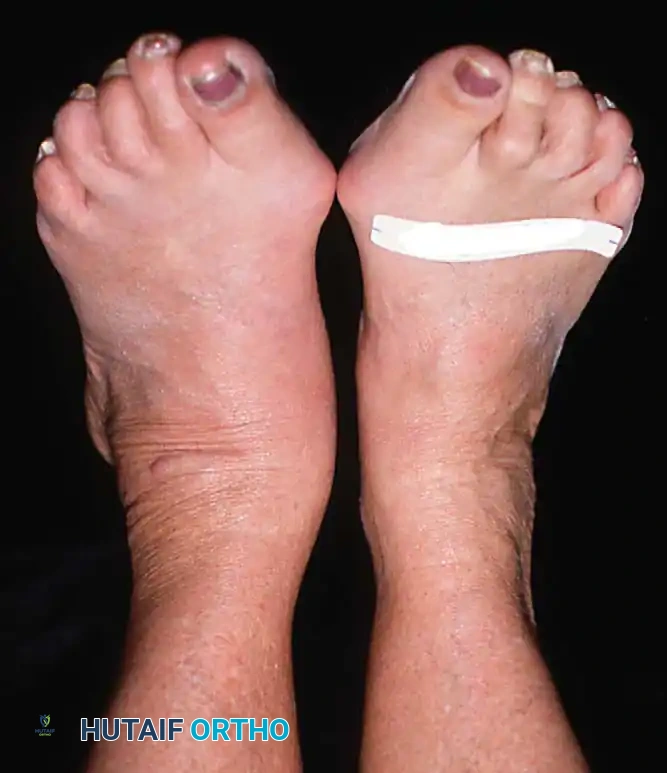

Observe the patient from the anterior and posterior aspects while standing. Look for the classic "too many toes" sign from behind, indicative of severe midfoot abduction.

- Clinical Findings: Loss of PTT function resulting in a flexible flatfoot deformity (hindfoot valgus, midfoot abduction). Mild lateral sinus tarsi pain may begin to manifest.

- Clinical Findings: A fixed, rigid hindfoot valgus and midfoot abduction deformity. Significant lateral sinus tarsi impingement pain is the primary complaint.